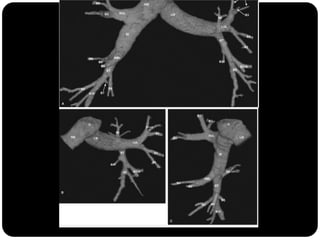

BRÔNQUIOS

PRINCIPAIS

LOBARES

SEGMENTARES

Vias aéreas

Traquéia

Brônquios –

Bronquíolos

Alvéolos

 Brônquios principais originam-se da traquéia

na carina;

 Brônquio direito: ângulo mais obtuso com o

eixo longo da traquéia;

 Direito(2,2cm) mais curto que o

esquerdo(5cm);

BPD: BLSD

BI - BLM

BI – BLID

BPE: BLSE

BLIE